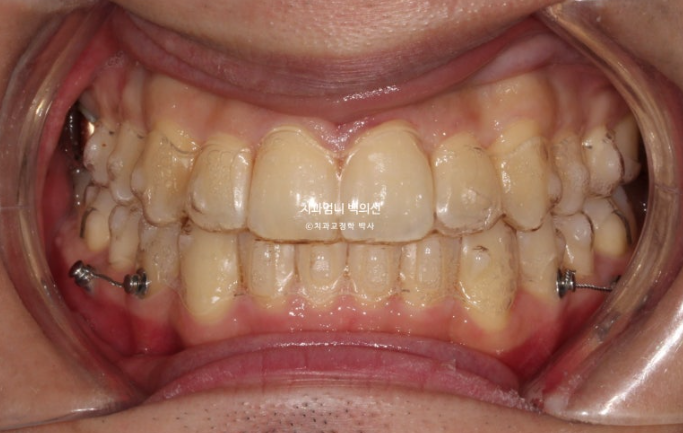

22.10

중심선 불일치가 보입니다.

골격적 비대칭은 경미하지만 앞니 중심선이 많이 달라 비대칭감을 크게 느끼고 있는 상태입니다.